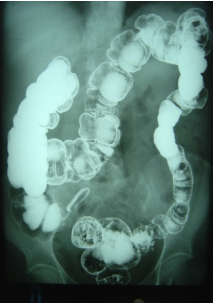

Paciente do sexo masculino, 55 anos, procura serviço de pronto atendimento com queixas de dor abdominal importante, principalmente na fossa ilíaca esquerda associado a febre a 24 horas. Refere que já apresenta sintomas de dor abdominal leve há cerca de um ano associado à constipação intestinal. Tem consigo um exame que realizou há cerca de 30 dias.

Diante deste quadro clínico, o exame mais indicado para avaliação e diagnóstico do paciente é: